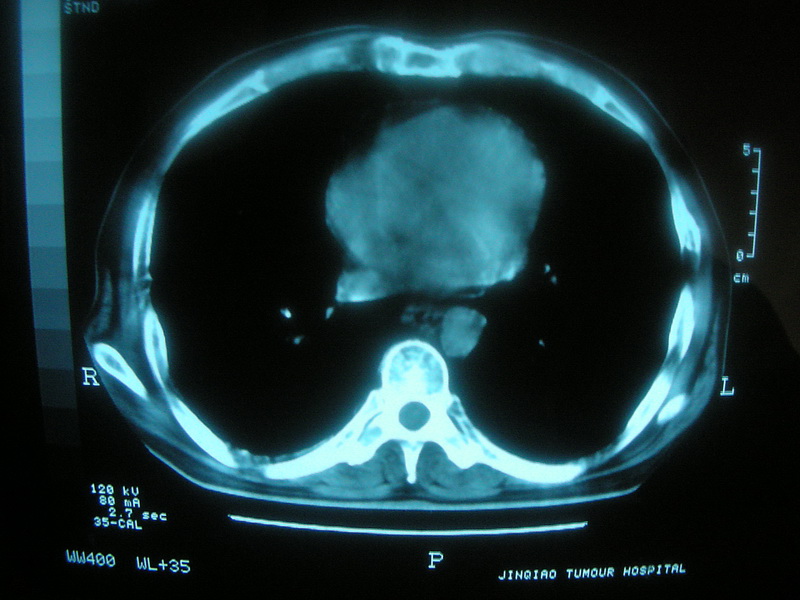

标题: CT11692:男,63岁,糖尿病史15年.抗炎治疗7天,病情 [打印本页]

标题: CT11692:男,63岁,糖尿病史15年.抗炎治疗7天,病情

请老师看看是结核还是炎症?

双肺继发性肺结核伴感染!

糖尿病首先考虑结核并感染。

考虑双肺继发性肺结核。